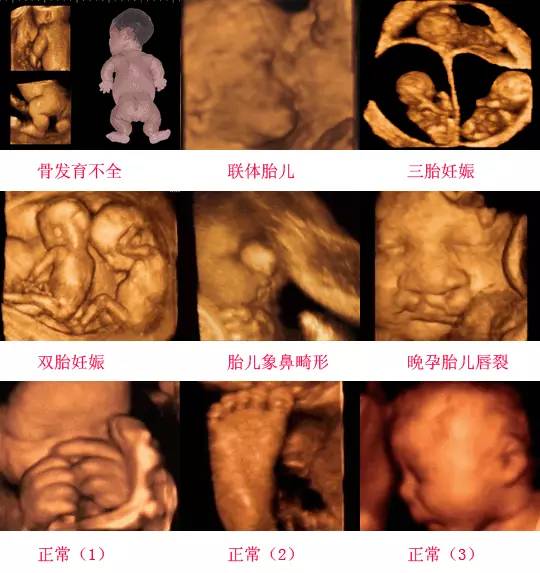

四維彩超是一種先進(jìn)的醫(yī)學(xué)影像技術(shù),通過實(shí)時(shí)觀察胎兒在母體內(nèi)的活動(dòng)情況,為醫(yī)生提供了豐富的診斷信息,在四維彩超下,我們可以清晰地觀察到胎兒的蛋蛋(睪丸)的形態(tài)、位置和大小等特征,胎兒蛋蛋是男性生殖系統(tǒng)的重要組成部分,對于胎兒的生長發(fā)育具有重要意義。

在四維彩超下,胎兒蛋蛋呈現(xiàn)出特定的形態(tài)和外觀,通常情況下,胎兒蛋蛋呈現(xiàn)出圓形或橢圓形,表面光滑,內(nèi)部回聲均勻,隨著胎兒的發(fā)育,蛋蛋會逐漸增大,并呈現(xiàn)出明顯的性別特征,醫(yī)生可以通過四維彩超技術(shù),對胎兒蛋蛋的大小、形態(tài)和位置進(jìn)行評估,以判斷胎兒生殖系統(tǒng)的健康狀況。

胎兒蛋蛋的發(fā)育是一個(gè)復(fù)雜的過程,受到多種因素的影響,在胎兒發(fā)育的早期階段,蛋蛋位于腹腔內(nèi),隨著胎兒的生長發(fā)育,蛋蛋逐漸下降至陰囊,這個(gè)過程受到激素、遺傳和環(huán)境等多種因素的影響,在四維彩超的觀測下,我們可以實(shí)時(shí)了解胎兒蛋蛋的發(fā)育過程,及時(shí)發(fā)現(xiàn)異常情況并采取相應(yīng)的治療措施。

四維彩超技術(shù)在評估胎兒蛋蛋發(fā)育方面具有重要意義,通過四維彩超,醫(yī)生可以實(shí)時(shí)觀察胎兒蛋蛋的形態(tài)、位置和大小等特征,了解胎兒生殖系統(tǒng)的發(fā)育情況,四維彩超還可以幫助醫(yī)生發(fā)現(xiàn)可能的異常情況,如睪丸未降、睪丸囊腫等,為及時(shí)采取治療措施提供依據(jù)。